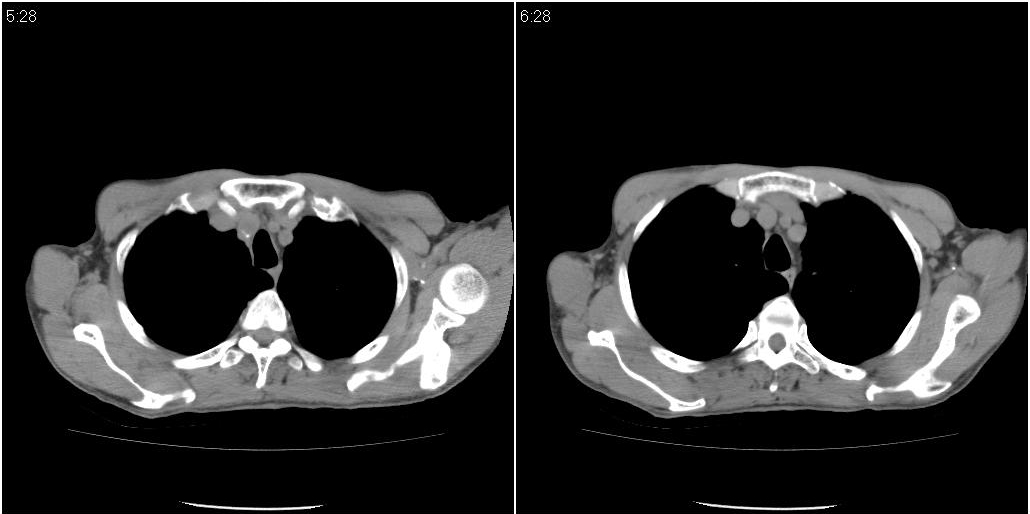

标题: ct增强:

右肺中叶阻塞性不张及肺炎,高度怀疑支气管占位,建议纤支镜检查!

右中肺阻塞性炎症,建议纤支镜!双下支扩感染。

1)右肺中叶慢性炎症并支气管扩张,节段性肺不张。2)两肺下叶支气管扩张。

1)右肺中叶慢性炎症并支气管扩张,节段性肺不张。2)左肺下叶支气管扩张